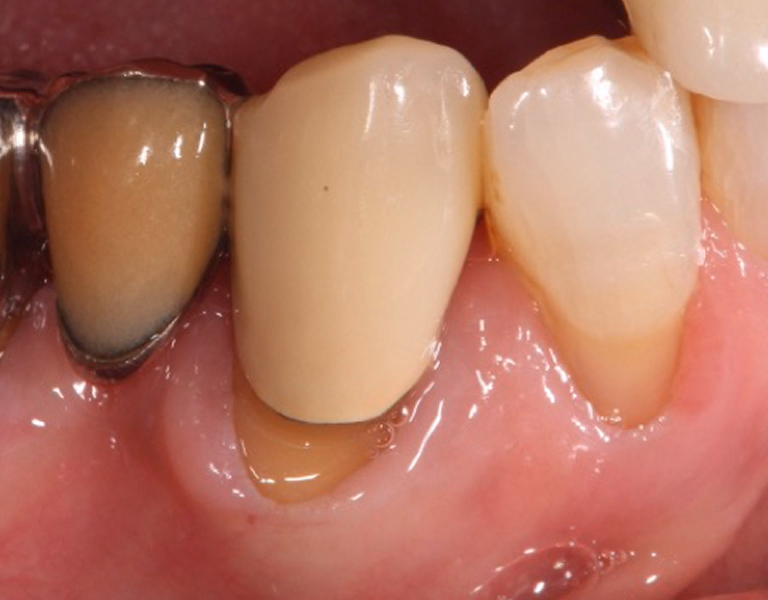

治療前後写真

治療前

治療後

80歳・男性

右下の歯がぐらぐらして咬めない

治療内容

- ① 重度歯周病のため抜歯 → 治癒後プランニング

- ② 1次手術時に骨造成を併用してインプラント埋入

- ③ 3ヶ月後、2次手術時に歯肉移植(歯肉補強術)を併用

- ④ 最終補綴装着後、メンテナンスへ移行

約5ヶ月

450,000円

清掃・メンテナンス不良でインプラント周囲炎・感染・脱落の可能性/術後の痛み・腫脹・出血

医院コメント

骨造成と歯肉補強を段階的に行い、清掃性・耐久性の高い周囲組織を再建。

埋入から15年経過時点でも良好に機能。